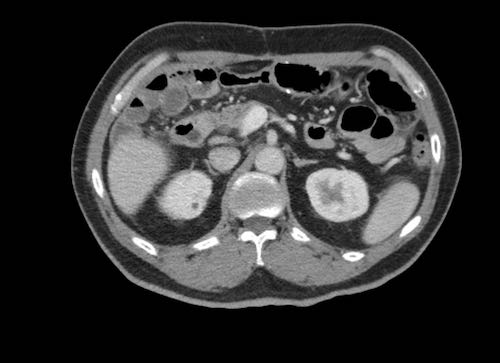

Ca lâm sàng 2

Cuộn qua các lát cắt.

Bạn có thể phát hiện tất cả các tổn thương cấy ghép phúc mạc không?

.jpeg)